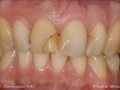

As Facetas Cerâmicas (lentes de contacto dentárias ou laminados), permitem corrigir da maneira mais estética e conservadora possível, problemas de forma e tamanho, côr e posição dos dentes, bem como substituir restaurações antigas e inestéticas.

São aderidas químicamente ao esmalte dentário de uma forma permanente, com o objectivo de melhorar a estética dos nossos pacientes.